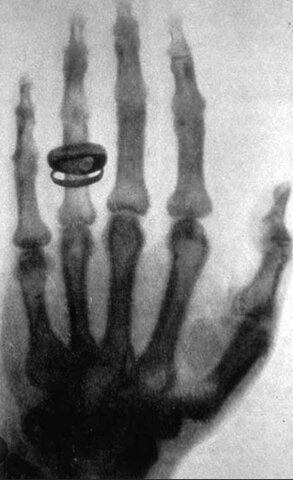

• Los rayos x

Los rayos x

El 8 de noviembre de 1895, el profesor Wilhem Conrad Röntgen descubrió los rayos x. Wilhem le hizo la primera radiografía a la mano de su mujer.